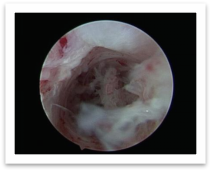

Case 1 : Effect of platelet-rich plasma gel on intrauterine adhesions